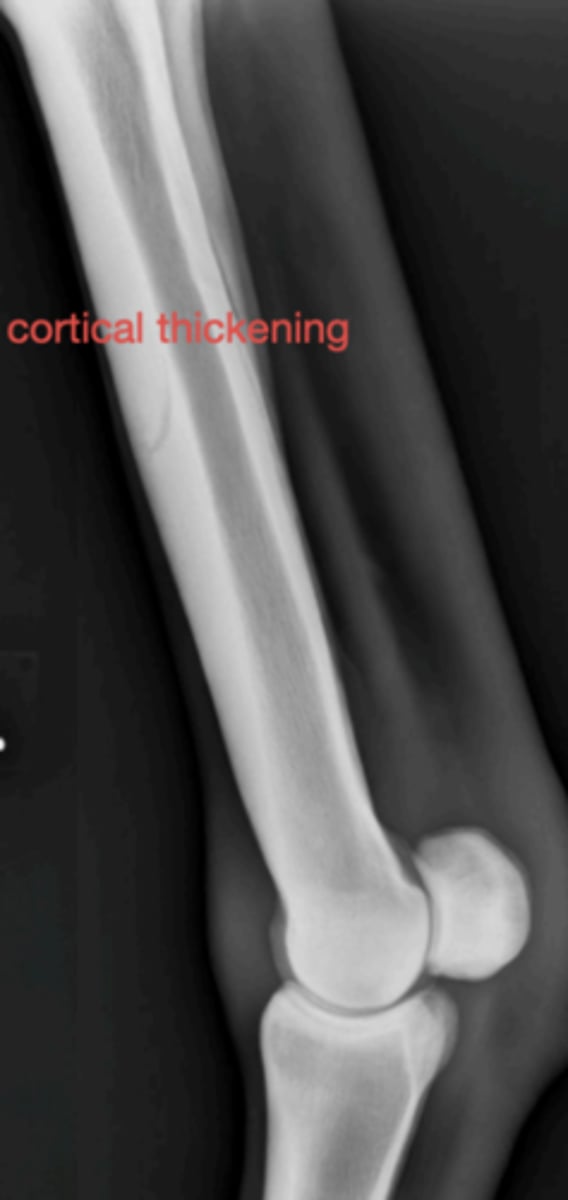

Metacarpal periositis

3 y/o horse with metacarpal pain; radiograph shows bone thickening- what caused this?